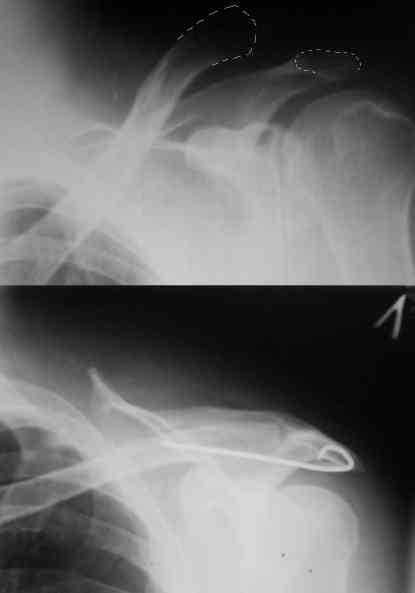

Внешний вид больного (травма: 09.10.2007, операция: 11.10.2007) Ориентиры доступа: овальный – пальпируемый акромиальный конец ключицы, линейный – операционный разрез

Введение крючка в подготовленный канал Дистальная часть крючка подведена под акромион и фиксирована на нем путем загибания (вывих ключицы устранен)

Изготовление крючка из стержня.